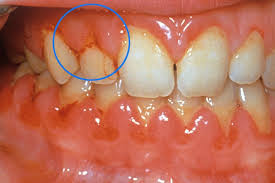

- 치은염(잇몸염증): 치석, 치태로 인한 세균 감염

- 치주염(잇몸뼈 염증): 잇몸염증이 심해져 잇몸뼈까지 손상

| 치은염 | 잇몸 붉어짐, 출혈 동반 | 스케일링, 위생관리 |

| 치주염 | 잇몸이 내려앉고 치아 흔들림 | 치주치료, 잇몸수술 |